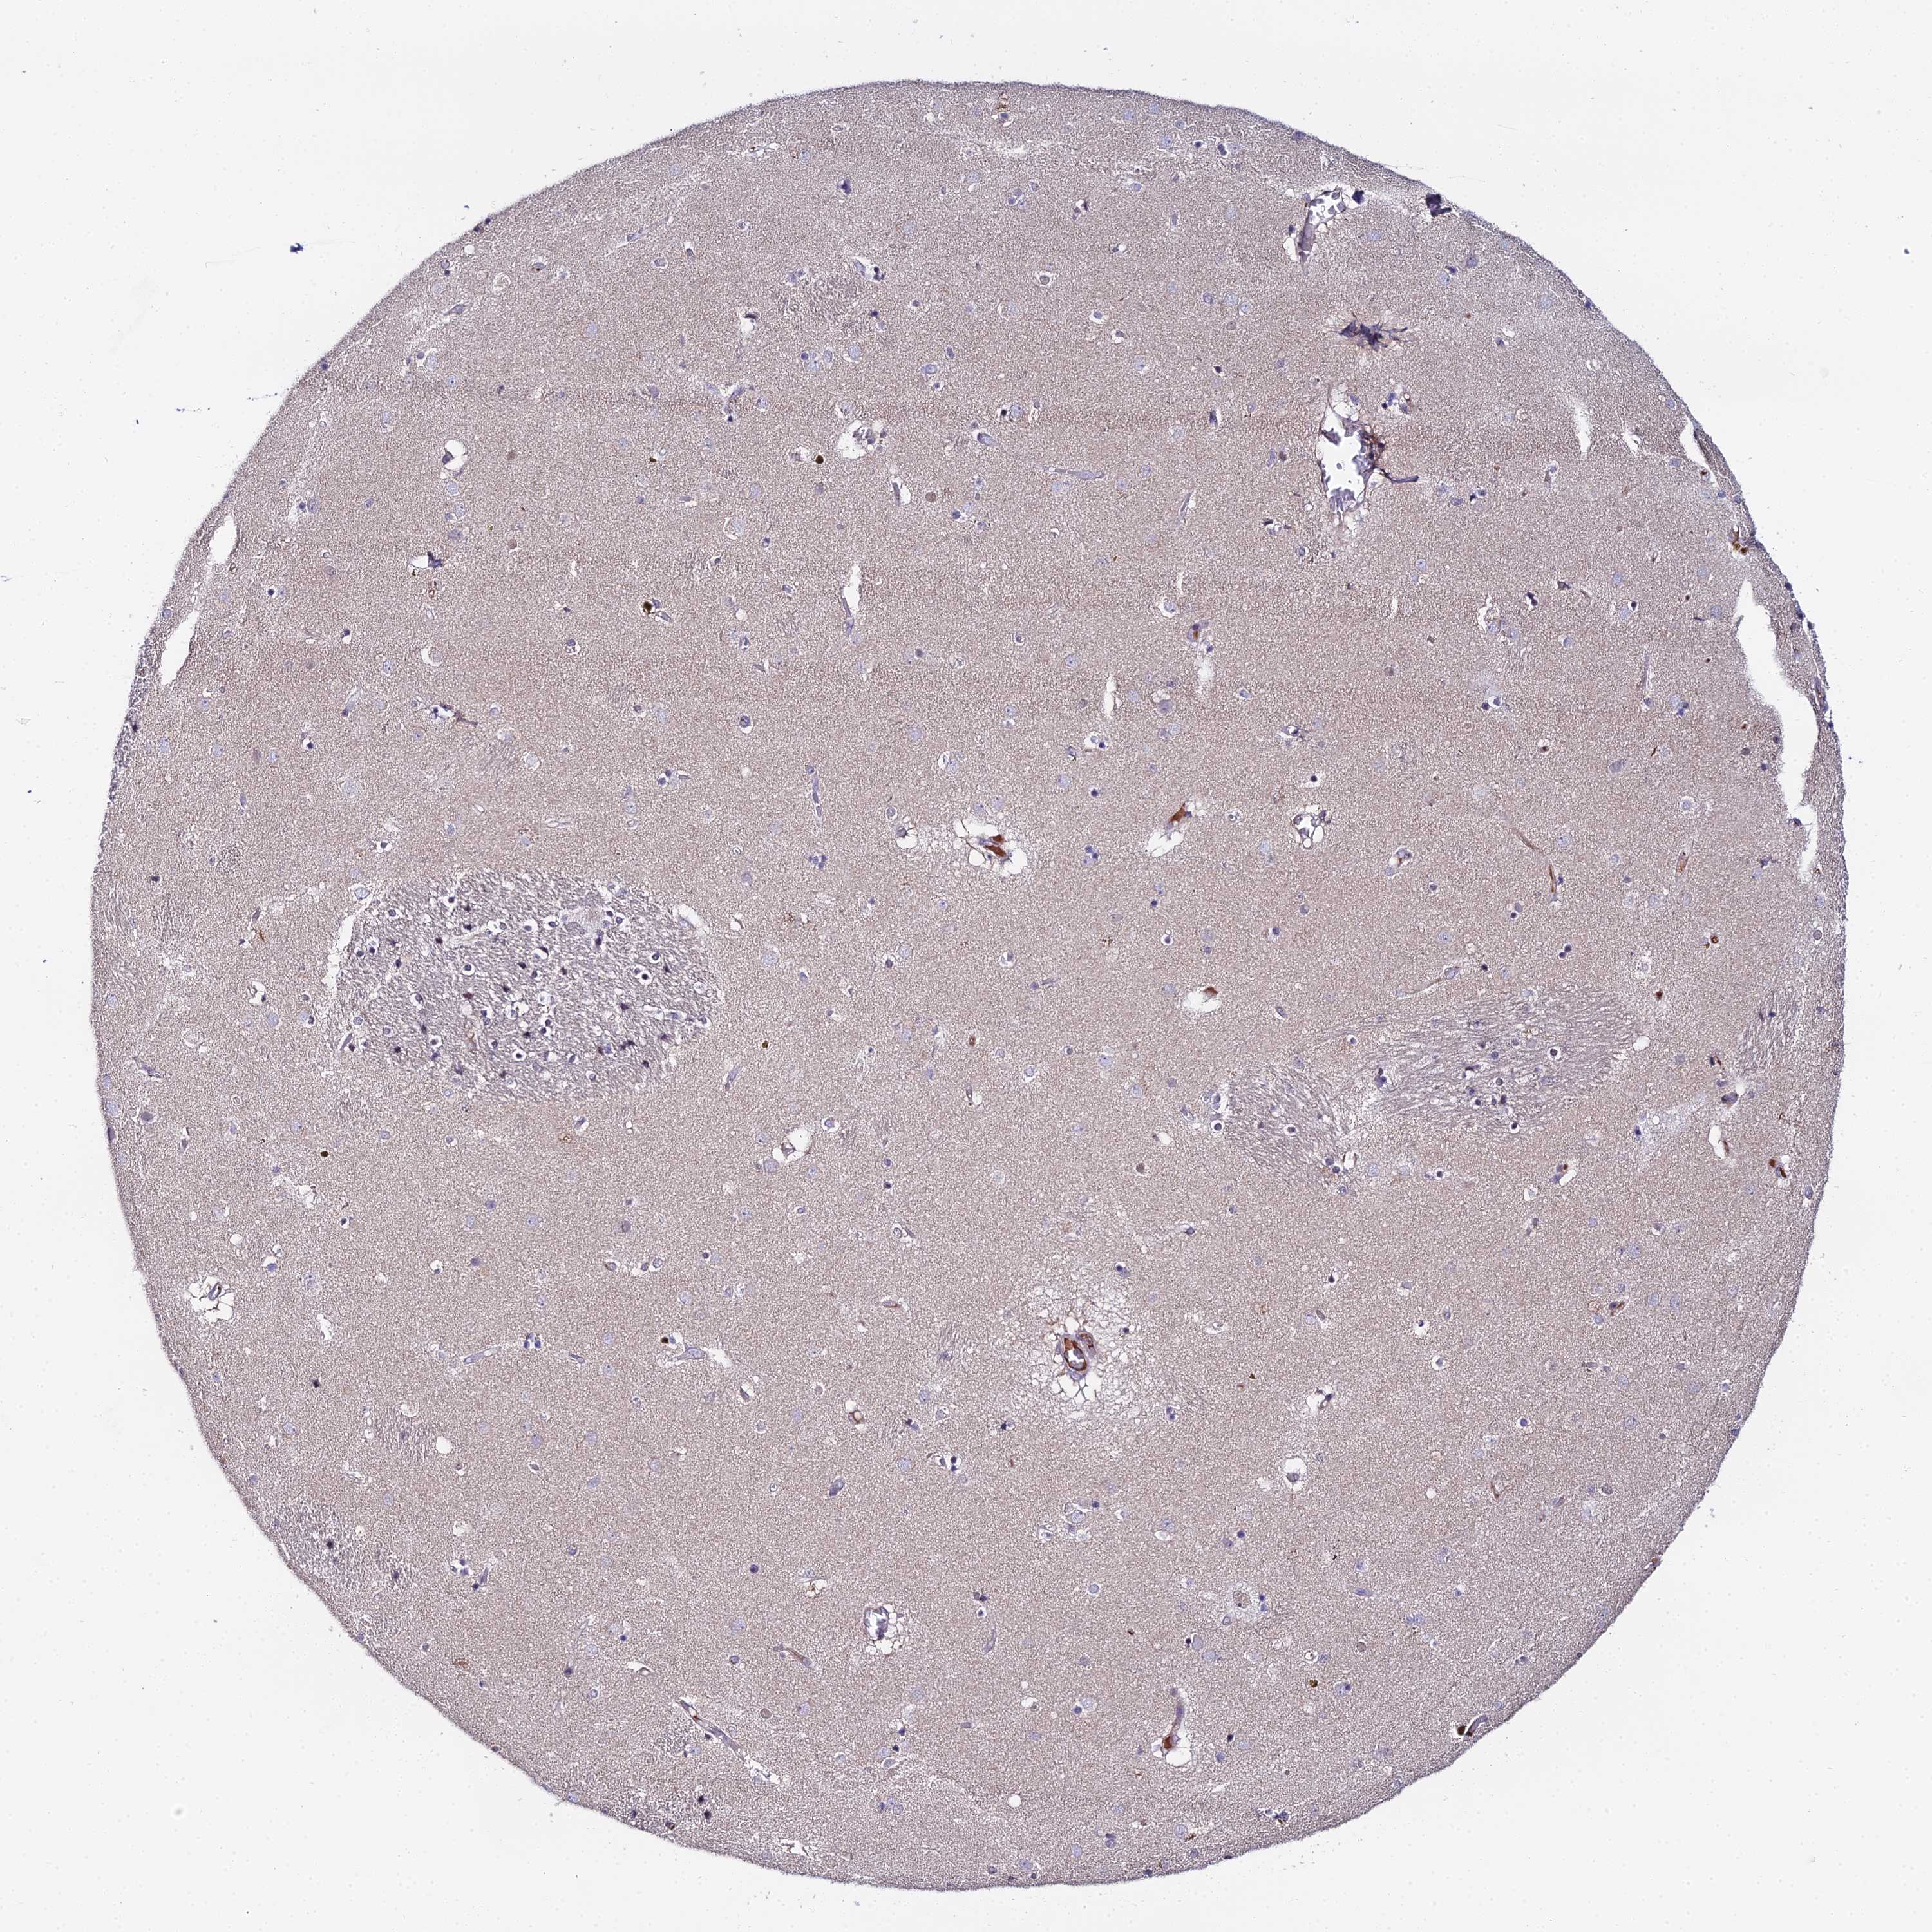

Antibody staining in the annotated cell types in the current human tissue is reported as not detected, low, medium, or high. This score is based on the staining intensity and fraction of stained cells.